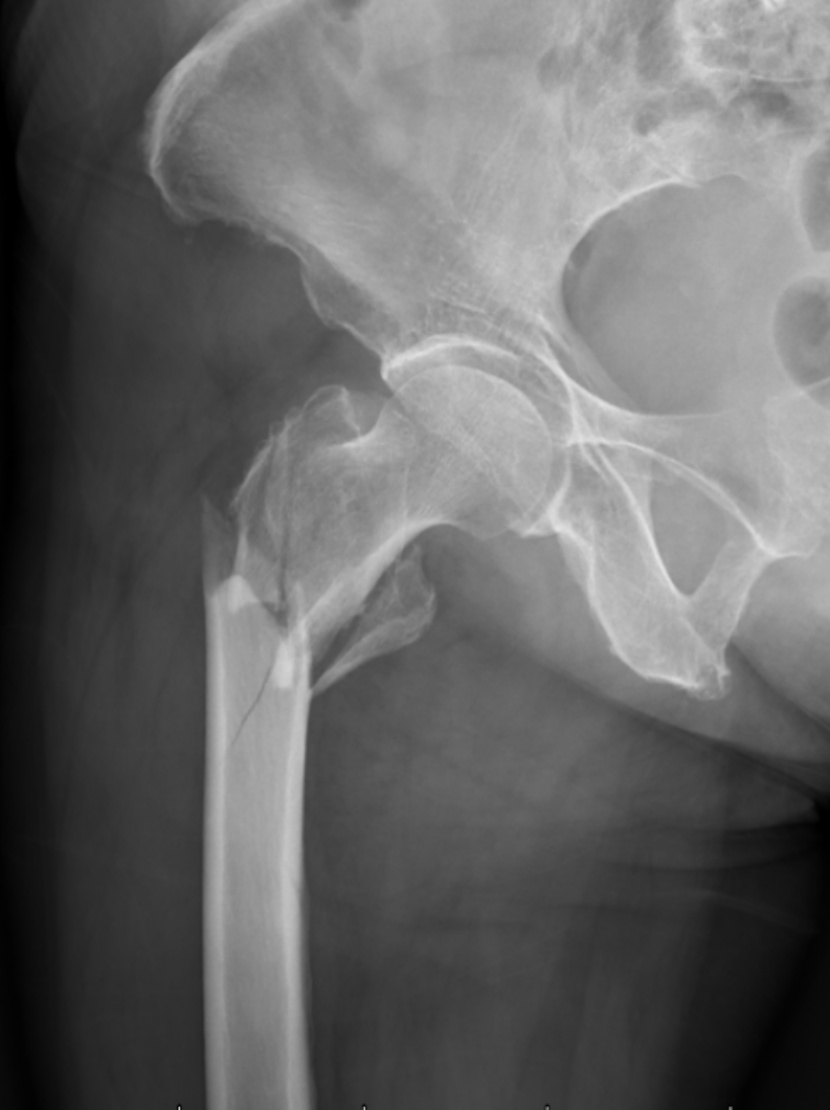

典型病例影像学表现见图1~10。图1为86岁女性右侧股骨转子间骨折(Evans Ⅲ型)患者,术前X线示骨折断端部分错位,术后X线示骨折位置可以及假体位置良好;图2显示了一名81岁男性患者,诊断为左侧股骨转子间骨折,类型为Evans V型,合并股骨干陈旧性骨折。患者接受了生物型加长柄半髋关节置换手术,并进行了股骨近端的钢丝捆扎内固定。术后X线示假体位置良好,股骨近端予钢丝捆扎固定;图3为87岁女性左侧股骨转子间骨折(Evans V型)患者,术后X线示假体位置良好,股骨大小转子骨折位置可,钢丝捆扎固定在位有效;图4为75岁女性左侧股骨转子间骨折(Evans V型)患者,术前X线示左侧股骨转子间骨折PFNA术后、骨折未愈合、内固定断裂。术后假体匹配良好,股骨近端钢丝内固定稳定可靠;图5为75岁男性左侧股骨转子间骨折(Evans IV型)患者,术后股骨大转子出现轻度位移,假体位置正常。图6为87岁男性左侧股骨转子间骨折(Evans V型)患者,给予DAA入路加长柄半髋关节置换,术前X线片,清晰地显示出左侧股骨转子间的骨折情况,术后X线影像,显示股骨的大小转子骨折位置良好,钢丝内固定装置在位稳定,假体位置良好;图7为77岁女性右侧股骨转子间骨折(Evans V型)患者,术前X线片显示右侧股骨转子间存在骨折且股骨大小转子均有累及和移位,术后X线片显示股骨小转子轻度移位,内固定装置位置稳定,假体位置良好;图8为70岁男性左侧股骨转子间骨折(Evans III型)患者,术前的X线片,清晰地显示了左侧股骨转子间的骨折情况,股骨近端髓腔钙化灶,术后假体位置满意;图9为77岁女性右侧股骨转子间骨折(Evans V型)患者,术前X线片,显示右侧股骨转子间及转子下部位骨折情况。术后假体匹配良好;图10为71岁男性右侧股骨颈骨折(Evans IV型)患者,术前X线片,显示右股骨转子间骨折的情况;术后X线表明股骨的大转子和小转子骨折位置保持良好,内固定装置稳固,术后假体位置正常。

(a) (b)

Figure 4. A 75-year-old female patient with left intertrochanteric fracture of the femur (Evans V type). (a) Before surgery; (b) After surgery